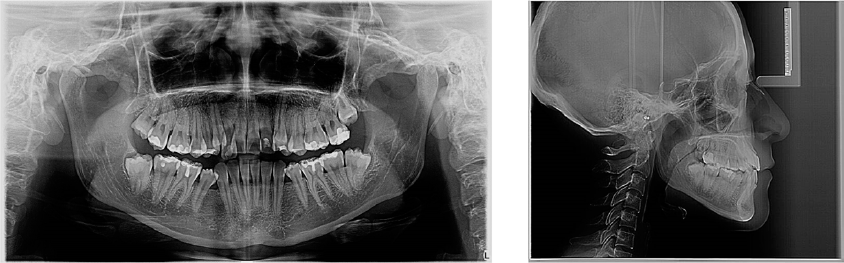

En el análisis facial se determinó una paciente dolicofacial con el tercio inferior aumentado, exposición disminuida de los dientes anteriores superiores al sonreír y perfil recto (Figura 1). A la exploración clínica se identificó dentición permanente con ausencia de los dientes 34 y 44, periodonto reducido estable, mucosa bien irrigada, frenillos bien implantados, líneas medias no concordantes, apiñamiento superior severo e inferior moderado; dientes 13 y 23 en supraoclusión Clase III molar, y mordida cruzada unilateral (Figura 2). Se solicitaron auxiliares diagnósticos incluyendo ortopantomografía y radiografía lateral de cráneo (Figura 3).

Figura 3 Estudios iniciales de ortodoncia, de izquierda a derecha, ortopantomografía y lateral de cráneo.

En la ortopantomografía se observaron 30 dientes; 28 erupcionados, terceros molares inferiores impactados, se confirmó la ausencia de los dientes 34 y 44, restauraciones extensas en 15 y 25. La paciente presentaba dilaceración y longitud radicular disminuida en los dientes 12 y 22. La relación corona-raíz en centrales superiores era 1:1 y existía una pérdida del reborde óseo en la zona de anteriores superiores e inferiores. El análisis cefalométrico reveló una Clase I esquelética con exceso vertical del maxilar y crecimiento horizontal (Tabla 1).